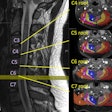

MRI may help guide brachial plexus surgery

August 26, 2025